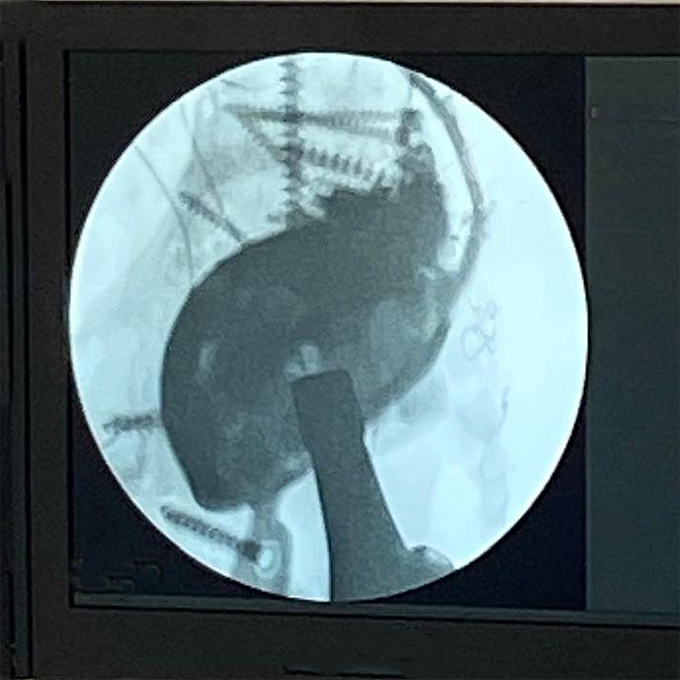

Intraoperative fluoroscopic assessment during definitive reconstruction.

During reimplantation, removal of the spacer and prior tectoplasty exposed a Paprosky IIIA acetabular defect. A complete posterior wall deficiency combined with a significant superior acetabular roof defect resulted in translational instability of the trial component in both cranio-caudal and anteroposterior directions. Cranio-caudal stability was achieved using a cranial trabecular titanium augment (TrabecuLink Augments). However, anteroposterior instability persisted.

The decisive step in reconstruction was the mechanical integration of a PPR-type acetabular cage with the trabecular titanium augment. The flanges of the MobileLink PPR were connected directly to the augment using 4.5 mm screws, transforming two independent components into a unified structural construct.

This integrated configuration restored stability in both planes and allowed early full weight-bearing.

On the femoral side, a LINK MP stem combined with an MP 2.0 metaphyseal component (38 mm offset) was implanted. Given the multiply operated hip and compromised soft tissues, a dual mobility articulation (MobileLink Dual Mobility Insert) with ceramic head was chosen to reduce dislocation risk.